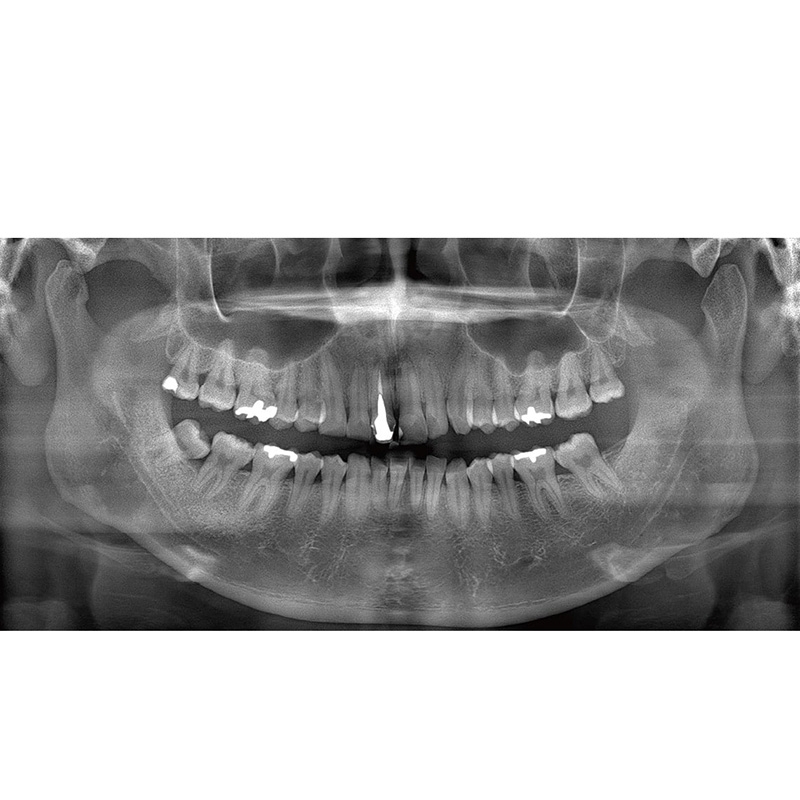

Information / DémonstrationPanoramique 2D

Veraview (IC5 HD) Données Techniques

Mode High-Speed - 5,5 sec./192 µm

Mode High-Definition - 10 sec./96 µm - Visée laser: